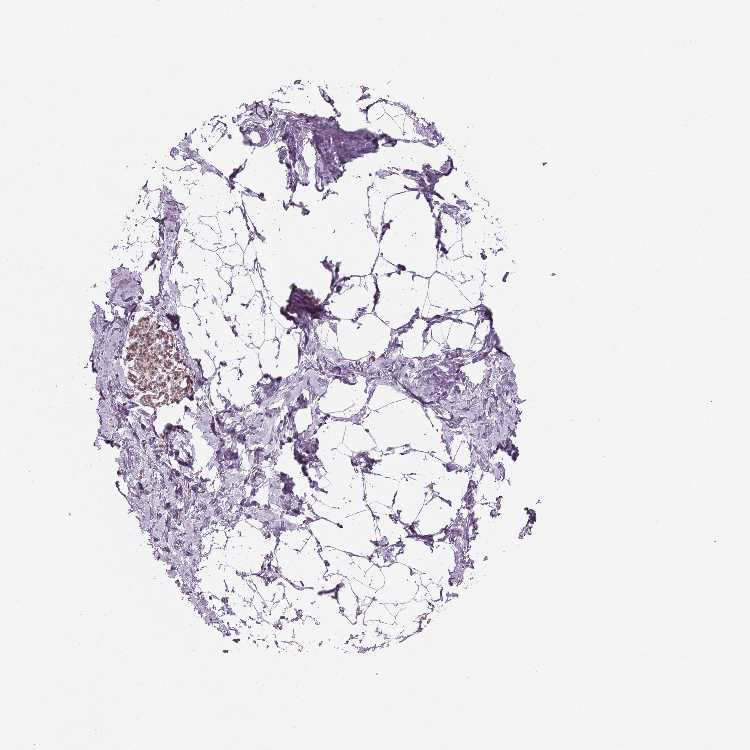

Female, age 52

Breast sample 373

nTPM: 7.9

Cell types%

Glandular cells:

15

Adipocytes:

5

Other cell types:

80

overview

Female, age 80

Breast sample 390

nTPM: 7.6

Female, age 47

Breast sample 405

nTPM: 8.9

90

Female, age 38

Breast sample 410

nTPM: 6.8

40

55